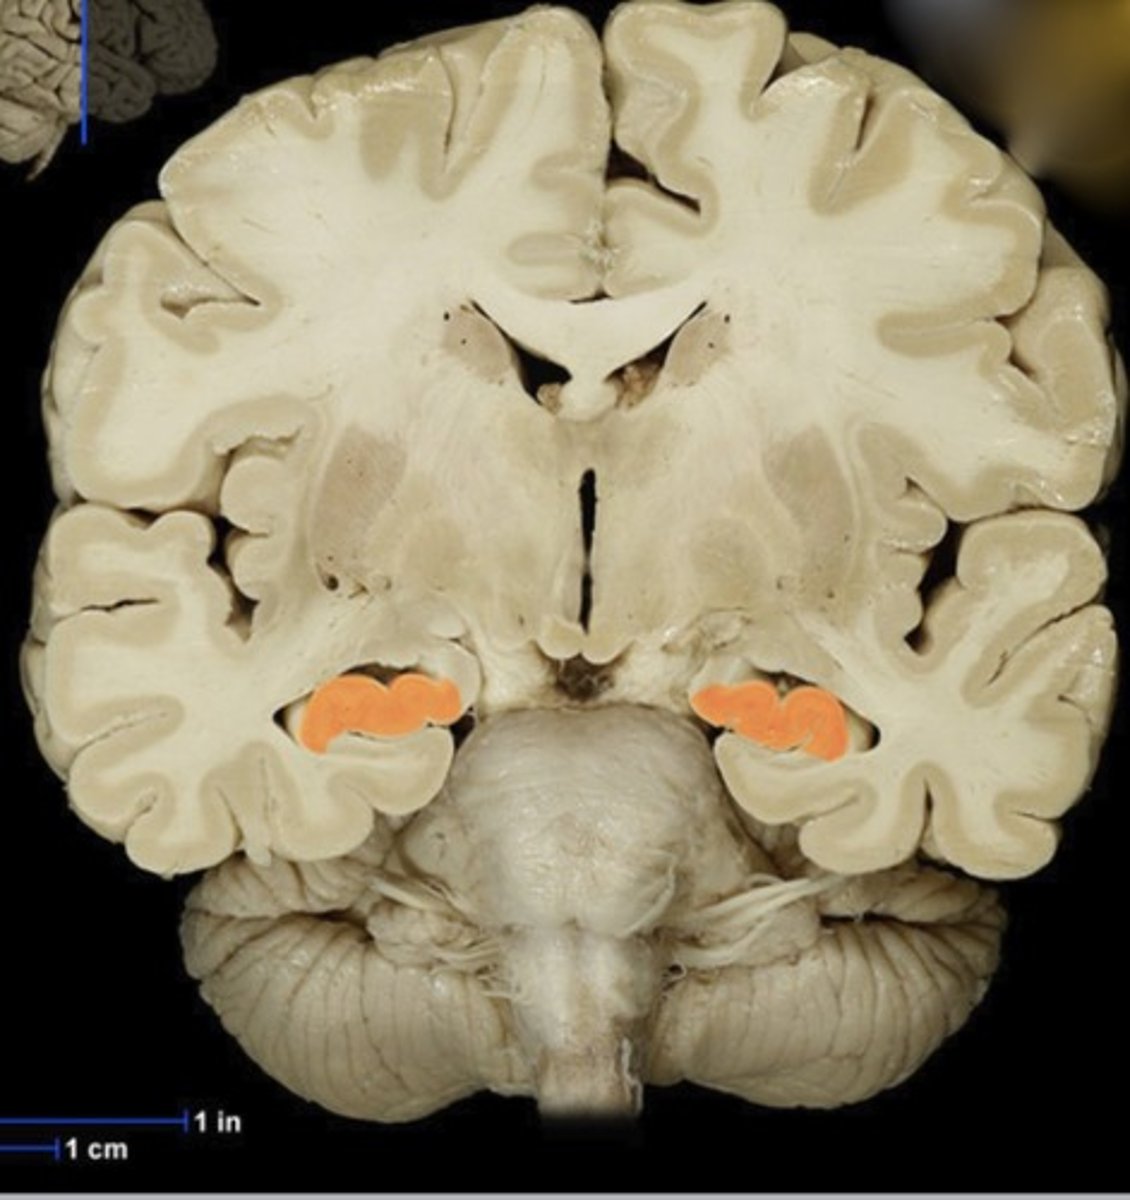

Name this structure

Hippocampus

Name this structure